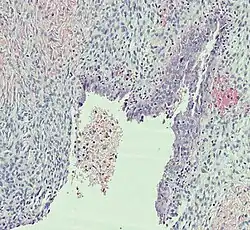

Histopathology

In case an ovarian cyst is surgically removed, a more definite diagnosis can be made by histopathology:

Type Subtype Typical microscopy findings Image

Functional cyst Follicular cyst

Corpus luteum cyst

Cystadenoma Serous cystadenoma Cyst lining consisting of a simple epithelium, whose cells may be either:[26]

• columnar and tall and contain cilia, resembling normal tubal epithelium

• cuboidal and have no cilia, resembling ovarian surface epithelium

Mucinous cystadenoma Lined by a mucinous epithelium

Dermoid cyst Well-differentiated components from at least two, and usually three,[11] germ layers (ectoderm, mesoderm and/or endoderm).[27]

Endometriosis At least two of the following three criteria:[28]

Borderline tumor Atypical epithelial proliferation without stromal invasion.[29]

Ovarian cancer Many different types, but generally severe dysplasia/atypia and invasion. Serous carcinoma.

Simple squamous cyst Simple squamous epithelium and not conforming to diagnoses above (a diagnosis of exclusion)